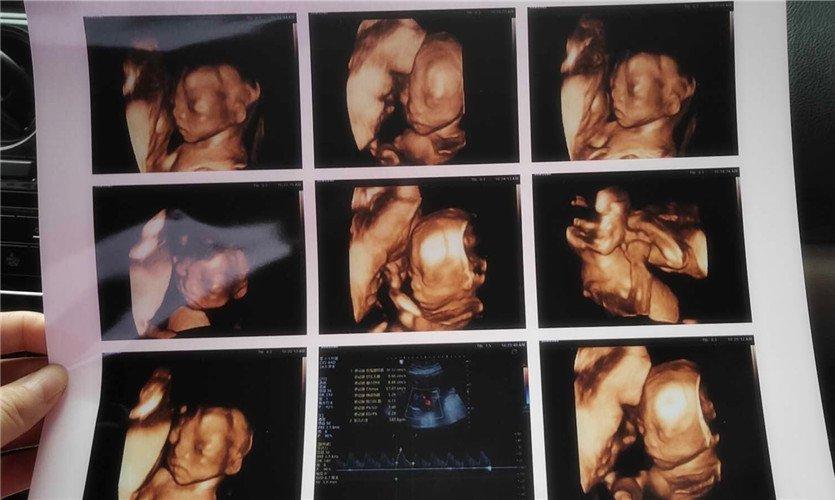

四維彩超是一種先進(jìn)的醫(yī)學(xué)影像技術(shù),通過(guò)實(shí)時(shí)觀察胎兒在母體內(nèi)的活動(dòng)情況,為醫(yī)生提供了豐富的診斷信息,在四維彩超下,我們可以清晰地觀察到胎兒的蛋蛋(睪丸)的形態(tài)、位置和大小等特征,胎兒蛋蛋是男性生殖系統(tǒng)的重要組成部分,對(duì)于胎兒的生長(zhǎng)發(fā)育具有重要意義。

在四維彩超下,胎兒蛋蛋呈現(xiàn)出特定的形態(tài)和外觀,通常情況下,胎兒蛋蛋呈現(xiàn)出圓形或橢圓形,表面光滑,內(nèi)部回聲均勻,隨著胎兒的發(fā)育,蛋蛋會(huì)逐漸增大,并呈現(xiàn)出明顯的性別特征,醫(yī)生可以通過(guò)四維彩超技術(shù),對(duì)胎兒蛋蛋的大小、形態(tài)和位置進(jìn)行評(píng)估,以判斷胎兒生殖系統(tǒng)的健康狀況。

胎兒蛋蛋的發(fā)育是一個(gè)復(fù)雜的過(guò)程,受到多種因素的影響,在胎兒發(fā)育的早期階段,蛋蛋位于腹腔內(nèi),隨著胎兒的生長(zhǎng)發(fā)育,蛋蛋逐漸下降至陰囊,這個(gè)過(guò)程受到激素、遺傳和環(huán)境等多種因素的影響,在四維彩超的觀測(cè)下,我們可以實(shí)時(shí)了解胎兒蛋蛋的發(fā)育過(guò)程,及時(shí)發(fā)現(xiàn)異常情況并采取相應(yīng)的治療措施。

四維彩超技術(shù)在評(píng)估胎兒蛋蛋發(fā)育方面具有重要意義,通過(guò)四維彩超,醫(yī)生可以實(shí)時(shí)觀察胎兒蛋蛋的形態(tài)、位置和大小等特征,了解胎兒生殖系統(tǒng)的發(fā)育情況,四維彩超還可以幫助醫(yī)生發(fā)現(xiàn)可能的異常情況,如睪丸未降、睪丸囊腫等,為及時(shí)采取治療措施提供依據(jù)。